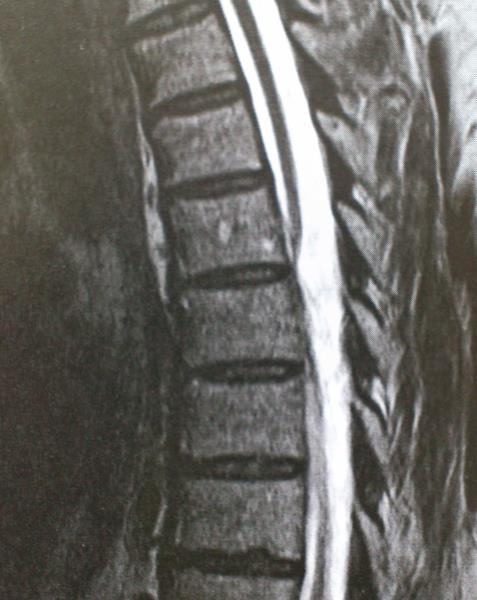

Ασθενής άνδρας 54 ετών με ιστορικό μυϊκής αδυναμίας και αισθήματος αιμωδιών κάτω άκρων από 4ετίας με προοδευτική επιδείνωση και εμφάνιση επιπροσθέτως διαταραχών σφιγκτήρων  παραπέμφθηκε στην κλινική μας μετά από τη διενέργεια MRI ΘΜΣΣ που ανέδειξε εικόνα πρόσθιας κήλης νωτιαίου μυελού στο επίπεδο Θ5-Θ6. Ο ασθενής υποβλήθηκε σε οπίσθια προσπέλαση. Μετά από διατομή αμφοτερόπλευρα των οδοντωτών συνδέσμων και της ραχιαίας αριστερής Θ5 ρίζας αναγνωρίσθηκε πρόσθια κήλη του νωτιαίου μυελού μέσα από έλλειμμα οπισθίου πέταλου διπλής (duplicate ) κοιλιακής (ventral) σκληράς μήνιγγας.Με μικροχειρουργική τεχνική επιτεύχθηκε διεύρυνση του ελλείμματος με αφαίρεση του οπισθίου πετάλου πέριξ αυτού και τελική ανάταξη του νωτιαίου μυελού.Ο ασθενής είχε ομαλή μετεγχειρητική πορεία και εξήλθε παρουσιάζοντας βελτίωση της μυϊκής ισχύς των κάτω άκρων. Η μετεγχειρητική μαγνητική τομογραφία ανέδειξε  ανάταξη του νωτιαίου μυελού με σήμα μυελοπάθειας στο επίπεδο της κήλης. Η χειρουργική αντιμετώπιση ασθενών με ιδιοπαθή κήλη του νωτιαίου μυελού έχει απόλυτη ένδειξη στην περίπτωση εμφάνισης μυϊκής αδυναμίας και προοδευτικής μυελοπάθειας και συνιστάται στην ανάταξη του νωτιαίου μυελού και την διεύρυνση ή αποκατάσταση του ελλείμματος της σκληράς μήνιγγος. Συνολικά οι ασθενείς τείνουν να βελτιώνονται μετά το χειρουργείο ακόμα και σε περιπτώσεις μακρόχρονου ιστορικού μυελοπάθειας.

Μετεγχειρητικός απεικονιστικός έλεγχος